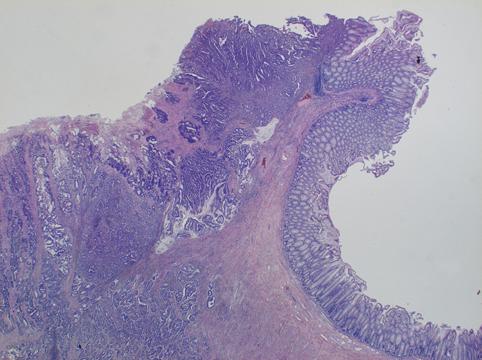

clasificación del pacienteTumor Epitelial Maligno/Adenocarcinoma

parte(separada por órganos)colon/transverso

método de exámenMicro

clasificación ectoscópica de tumoresTipo 3(Tipo ulcerado de bordes infiltrados)/

diámetro mayor del tumor40 -

grado de penetraciónss(a1)